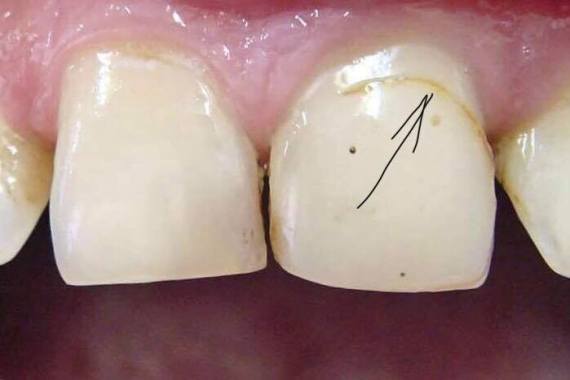

ЧОМУ ЧОРНІЄ ЗУБ ПІД ПЛОМБОЮ

Чому чорніє зуб під пломбою і чи може полікований зуб руйнуватись?

Якщо у вас нічого не болить і не турбує – навіщо йти до стоматолога? Так думає більшість людей, проте така точка зору є помилковою. Якщо «болить» – це вже крайній варіант. Більшість стоматологічних захворювань протікає безсимптомно і не створює жодного дискомфорту. Пацієнт впевнений, що у нього все гаразд (оскільки нічого не турбує), а насправді можуть…